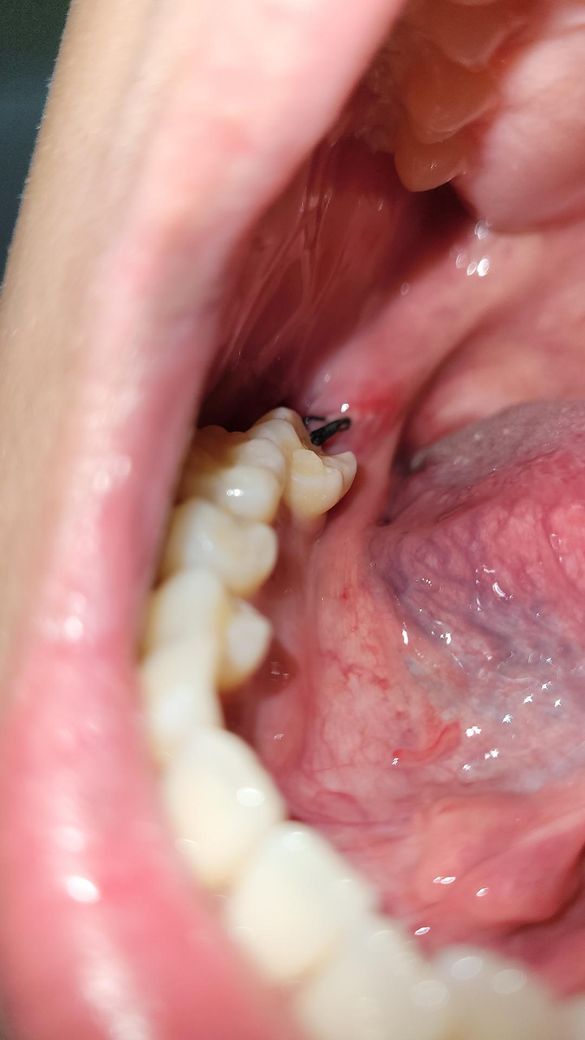

이거 혹시 드라이소켓 같은건가요?? 실밥이 풀린건가요...

이게 실밥이 풀린건지 안에 흰색이 보여서 그러는데 이게 멀까요... 아 진짜 사랑니 뽑은지는 3일 됐는데 바로 치과 가야할까요?? 아니면 어떡해야할까요

상처회복과정에서 자연스레 생기는 조직입니다. 그것들이 나중에 잇몸 살로 변하면서 아무는 것입니다. 걱정하지 않으셔도 돼고, 3일차면 거의 괜찮을테지만 혹시 모르니 떨어지거나 자극되지 않도록 주의하시고 음식물이 끼이면 물 가글로 빼주시면 좋습니다.

발치를 하고 나면 발치를 한부위가 아물면서 하얀색 가피등이 형성될수 있습니다. 문제가 되는것은 아니며 발치한 부위가 아물면서 생기는 증상입니다.

하얀색은 잇몸이 치유되는 조직으로 보이고, 실밥은 느슨해진 상태입니다. 드라이소겟은 참을수 없는 통증이 동반됩니다. 염려가 된다면 치과에 내원하여 소독을 받는것도 좋을것 같습니다. 건강하세요.

흰색 보이는 건 치유과정에서 생기는 염증,육아조직 같습니다

실밥은 밥먹다가, 양치하다가 지연스럽게 풀리기도 합니다